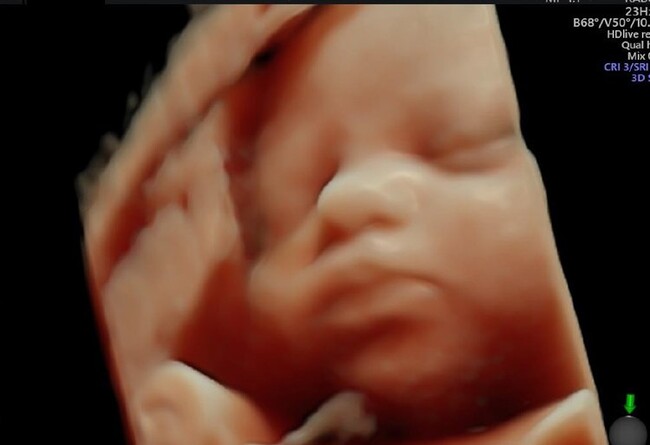

La nueva generación de ecógrafos de alta resolución mejora la capacidad diagnóstica y la detección de malformaciones fetales. Es el caso de la ecografía 5D que permite ver al bebé en el útero en cinco dimensiones, logrando una reconstrucción mucho más definida y realista del feto que las 4D o 3D.

De hecho, esta prueba no invasiva permite capturar imágenes tridimensionales en tiempo real del feto en el útero de la madre y usando gafas interactivas se puede ver un vídeo del bebé en 3D.

Esta prueba diagnóstica utiliza los ultrasonidos para generar imágenes tridimensionales que permiten comprobar cómo se está desarrollando el bebé en el útero mediante el estudio de su crecimiento y de la función placentaria. Ofrece la posibilidad de ver al niño en movimiento, pues se obtiene un vídeo del bebé generado a través de imágenes en 3D. Su software reduce las manchas, elimina el ruido de las imágenes y realza los bordes de los tejidos, dotando a la imagen del bebé de mayor resolución y nitidez y de unos tonos de sombras que dan un aspecto realista a los rasgos de la cara del feto, muy similar a su apariencia al nacer.

En comparación con la ecografía bidimensional habitual, la de 3D que permite ver la profundidad de la estructura anatómica del feto y la de 4D que permite observar los movimientos fetales, mientras que la 5D capta vídeos extremadamente realistas en tiempo real, con una vista detallada de las características del feto a través de imágenes que incluso pueden mostrar las tonalidades y matices de la piel.

La principal diferencia entre la ecografía 4D y la 5D es el tratamiento de las imágenes, que se muestran de manera más clara y con más texturas. Mientras que la 4D es conocida como la ecografía emocional, a la 5D se la llama 'el modo de vida', ya que se ve al bebé como si estuviera delante.